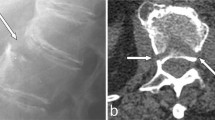

Conventional radiographs are the initial imaging study of choice. Plain radiographs are most reliable to determine the exact level of the lesion when the lowest rib is included in the image. Especially in AS patient presenting with localised pain after a trauma, a high index of suspicion is required [49]. Finkelstein et al. showed that a significant part of the spinal fractures is initially missed, allowing progression to pseudarthrosis [12]. The AL is revealed by osteolytic destruction with a surrounding zone of reactive sclerosis and vertebral osteophytes [9]. The spinal lesion can be confined to the vertebral body (transvertebral), through the disc space (transdiscal), or both (discovertebral) [36]. In transdiscal lesions, the disc space is conspicuously more radiolucent than its neighbour disc spaces which are fused. The lesions may be accompanied by fractures of the posterior elements, which generally can be exposed by lateral radiographs. An intervertebral vacuum phenomenon may be visible at the side of the lesion, and the disc space can be increased or narrowed. Angular kyphosis with or without spondylolisthesis in the AL is a regular prominent feature. In cases with a severe global thoracolumbar kyphotic deformity, the apex of the kyphosis is most often at the level of the AL (Figs. 2a and 3a). Flexion and extension radiographs may show motion in some cases. These radiological features are not pathognomonic for ALs and may also be seen in septic spondylitis or spondylodiscitis. Dihlmann et al. state that AL can be differentiated radiologically from an inflammatory spondylodiscitis by the demonstration of a circumscribed defect in one or two neighbouring vertebral bodies with varying degrees of narrowing of the intervening disc space, angular kyphosis of the affected spinal segment and an area of reactive sclerosis in the vertebral cancellous bone surrounding the defect [24].

Anteroposterior plain radiograph from an AL at the thoracolumbar junction in a 56-year-old female AS patient (a). A sagittal reconstructed CT image of the same patient shows central osteolysis surrounded by an irregular sclerotic zone (b). The lesion extends into the posterior elements and has resulted in narrowing of the spinal canal

Computed tomography (CT) imaging is superior to conventional radiographs in determining the extent of the lesion (Fig. 2b). CT imaging of an AL shows irregular vertebral or discovertebral osteolysis with surrounding reactive sclerosis [52]. CT can always accurately demonstrate fractures of the posterior elements or non-fusion of the facet joints. In addition to conventional plain radiographs, CT imaging is more sensitive in demonstrating vacuum phenomena and paraspinal swellings. The transversal imaging is used to determine the presence, location, severity and nature of spinal stenosis. Chan et al. described 18 AS patients with 22 spinal pseudarthrosis, who underwent conventional radiography as well as CT imaging. In 77% of the lesions, CT imaging provided data that were missed on conventional radiography. Therefore, CT offers considerable contributory advantages over conventional radiography in diagnosing AL complicating AS [52]. However, CT scanning had the disadvantage of irradiation, which should be considered when choosing the appropriate imaging method.